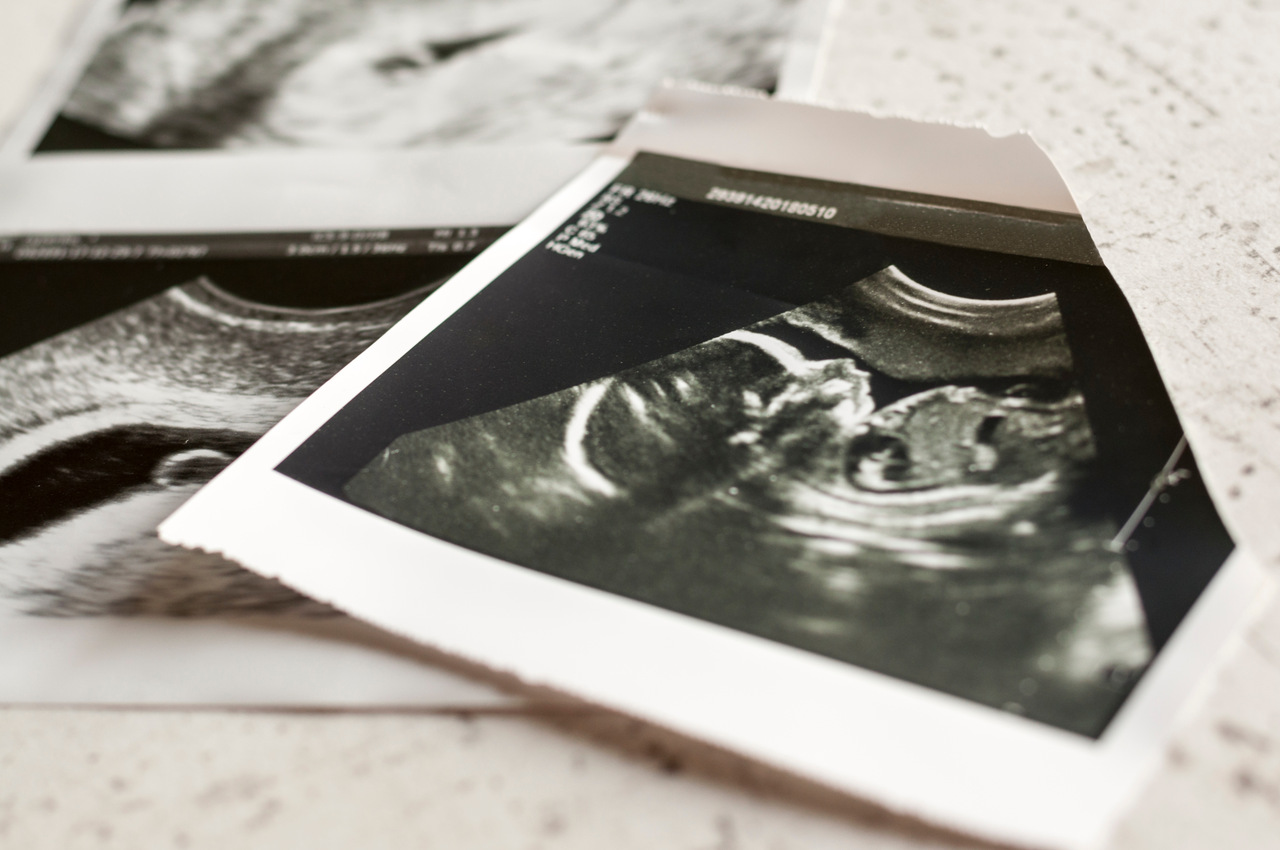

Membros como bracinhos, pernas e mãos já estão completamente formados, e a partir desse momento, o pequeno ganhará cada vez mais peso. Por isso, exames como o ultrassom morfológico são essenciais nessa etapa, além de muito aguardados pela família — já que, com ele, é possível ver os detalhes do feto.

- Também é o momento da realização do ultrassom morfológico do 2° trimestre (entre 20 e 24 semanas), que avalia toda anatomia fetal a fim de diagnosticar malformações;

- “Junto do morfológico, é realizado um ultrassom transvaginal para a medida do colo uterino e para rastrear gestantes com maior risco de parto prematuro.”